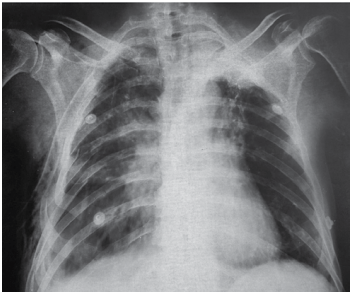

Paciente vítima de trauma moto versus auto foi diagnosticado com pneumotórax direito, e esse paciente foi drenado pelo médico que o atendeu. Ao assumir o plantão,

outro médico reavalia o paciente, que mantém queixa de

dor em hemitórax direito, taquipneia e murmúrio diminuído à direita, com saturação de 93% com 2L de oxigênio.

A radiografia realizada é a seguinte: